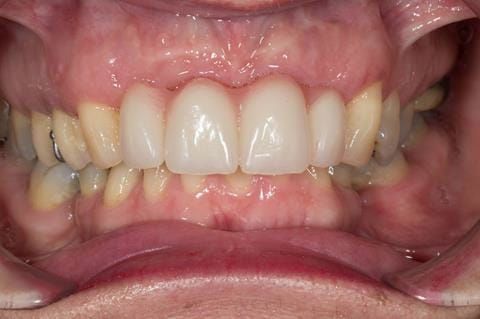

Following consultation and second discussion appointment the patient chose to have option 3 namely, a maxillary cobalt chromium based partial denture/protective occlusal splint. The clinical situation and treatment process is shown in detail below with photographs. The patient was successfully rehabilitated with this and her quality of life considerably improved. The clinical work was provided by Finlay and the technical work by Rowan.